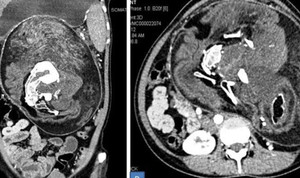

Đây là trường hợp mang song thai chung bánh rau, buồng ối, 2 dây rốn xoắn lấy nhau, cả 2 dây rốn đều bị thắt nút.

Song thai chung bánh rau đã nguy hiểm mà chung buồng ối còn nguy hiểm hơn rất nhiều. Song thai chung buồng ối đặc điểm là hai dây rốn nằm gần nhau nên khi thai nhi chuyển động dễ làm hai dây rốn xoắn vào nhau, thậm chí còn thắt nút dẫn tới mất tim thai nếu không được xử trí kịp thời.

Trường hợp ca song thai có hai dây rốn thắt nút vô cùng hiếm gặp, rất ít được mô tả trong y văn.

Mặc dù đã thăm khám và siêu âm theo dõi tình trạng thai phụ trong suốt thai kỳ, nhưng ngay khi đưa 2 em bé chào đời thành công, bác sĩ Bệnh viện Thu Cúc cũng rất ngạc nhiên khi lần đầu tiên chứng kiến ca sinh dây rốn xoắn lấy nhau và thắt nút ở cả 2 dây rốn.